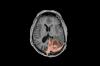

The seven projects and 11 investigators who will be funded examine a wide swath of neuroscience. There are projects exploring dementia, amyotrophic lateral sclerosis (ALS), chronic pain, multiple sclerosis and related immune diseases, anxiety and autism.

The Weill Awards fund science from the most basic to the most applied, fostering areas of science that can help patients through new therapeutics, diagnostics, imaging technology, biomarkers and computational methods. Hauser noted that the selection committee particularly rewarded projects that lead to tangible benefits for patients, including the likelihood that the study will have an immediate impact.